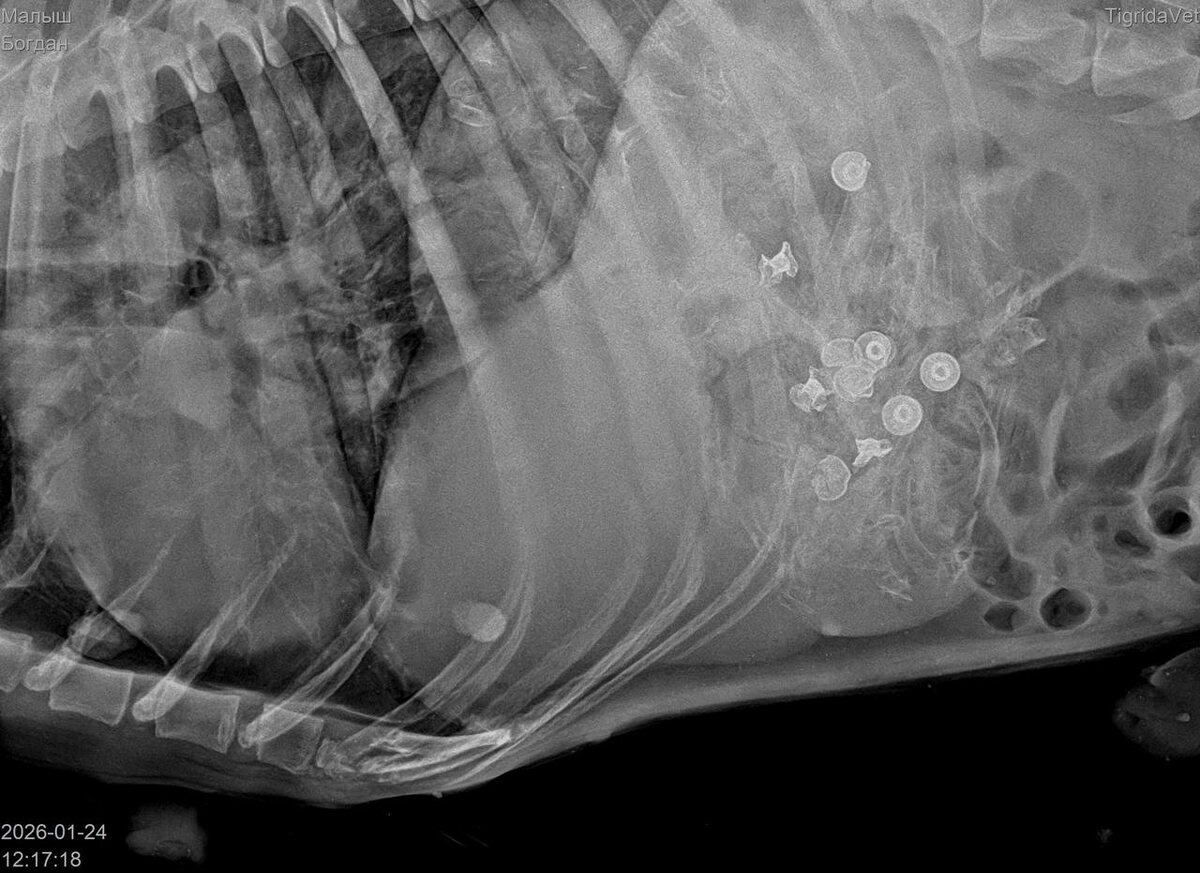

Был сделан рентген в нескольких проекциях.

Со слов врача, внутри было множество пуль. По его подсчётам уже их видно было 9. А возможно и больше.